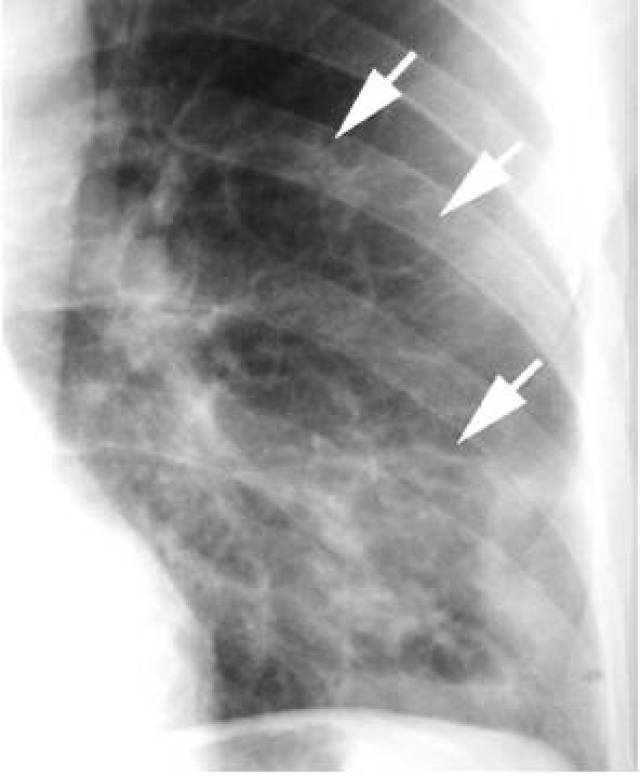

胸片显示边界不清的右肺门肿块(箭头),为典型的起源于肺门的肿瘤